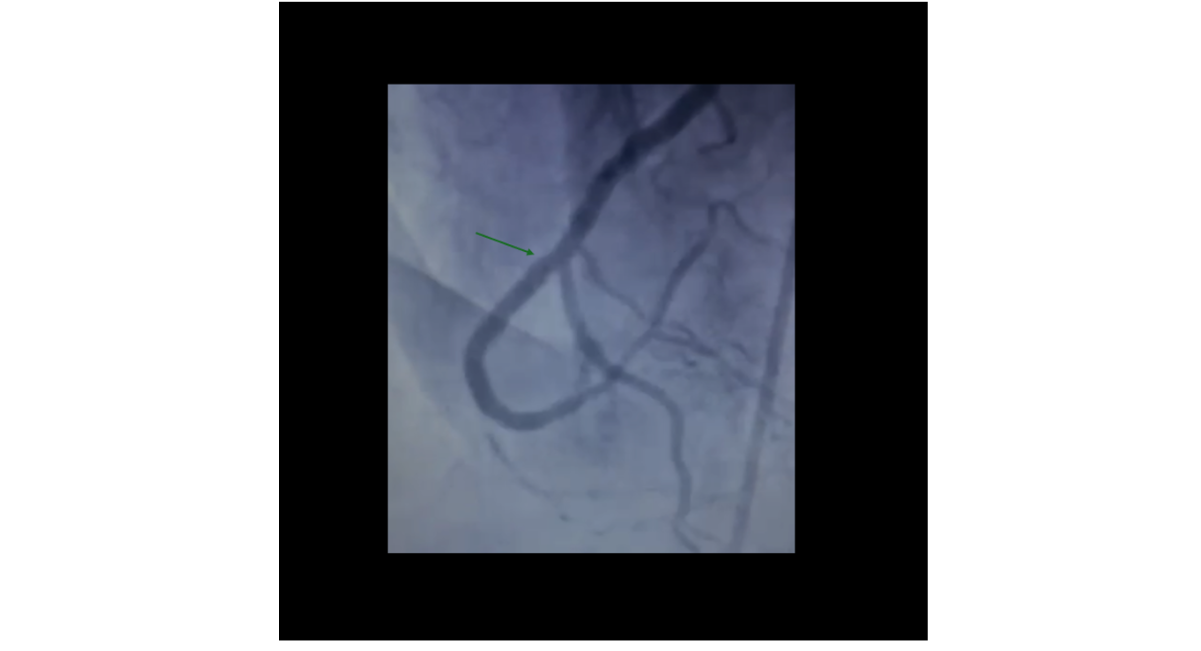

Diagnostic coronary angiography revealed mild non-obstructive disease in the left anterior descending (LAD) and left circumflex (LCX) arteries. The mid-RCA demonstrated a very short but heavily calcified CTO located at the level of the right ventricular (RV) branch, with both antegrade and retrograde collateral filling (Figure 1). Given persistent symptoms, objective ischemia, and suitable distal vessel target, CTO PCI was deemed appropriate.

Figure 1: Initial angiography showing CTO of the RCA, red arrow: distal RCA occlusion, green arrow: Posterior Descending Artery (PDA) occlusion.